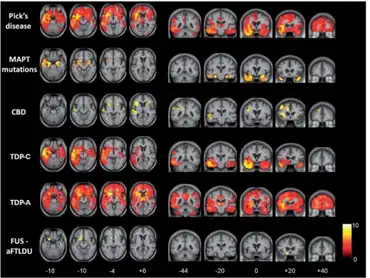

For diagnostic purposes, magnetic resonance imaging (MRI) and ([18F]fluorodeoxyglucose) positron emission tomography (FDG-PET) are applied. They measure either atrophy or reductions in glucose utilization. The three clinical subtypes of frontotemporal lobar degeneration, frontotemporal dementia, semantic dementia and progressive nonfluent aphasia, are characterized by impairments in specific neural networks.[12] The first subtype with behavioral deficits, frontotemporal dementia, mainly affects a frontomedian network discussed in the context of social cognition. Semantic dementia is mainly related to the inferior temporal poles and amygdalae; brain regions that have been discussed in the context of conceptual knowledge, semantic information processing, and social cognition, whereas progressive nonfluent aphasia affects the whole left frontotemporal network for phonological and syntactical processing.

- ↑ Schroeter ML, Raczka KK, Neumann J, von Cramon DY (2007). "Towards a nosology for frontotemporal lobar degenerations – A meta-analysis involving 267 subjects". NeuroImage. 36 (3): 497–510. doi:10.1016/j.neuroimage.2007.03.024. PMID 17478101. S2CID 130161.